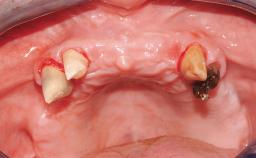

A fully edentulous 65-year-old woman was referred to our clinic for esthetic and functional dental rehabilitation. The patient presented with inadequate complete maxillary and mandibular prostheses, insufficient vertical dimension, and extensive tooth wear. The clinical examination and anamnesis showed no local or systemic contraindications, no signs or symptoms of bruxism, and an absence of smoking habits. The treatment proposed was implant placement in the mandibular interforaminal area and immediate loading with a fixed definitive prosthesis. A removable mucosa-supported complete prosthesis was indicated for the upper jaw, since its bone structure offered satisfactory retention and the financial condition of the patient disfavored a full-mouth implant-supported rehabilitation.

Case Type Edentulous Mandible

Jaw Mandible

Area Full-Arch

# of Implants 4